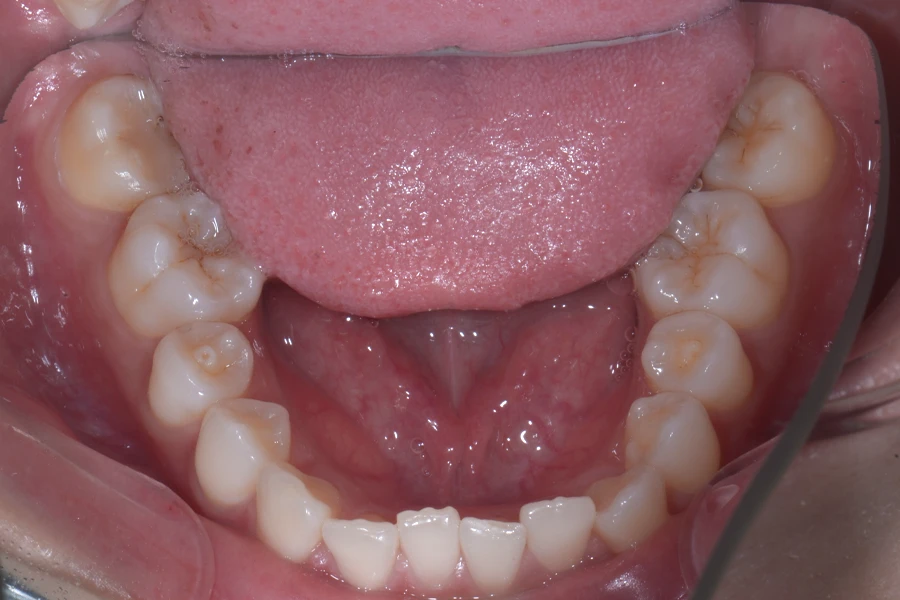

治療後

主訴 結婚式までに前歯を綺麗に整えたい

期間 10か月

費用 40万円(別途調整料)

デンタルローン80回 ¥5,800/月

治療内容 上下顎ラビアル矯正(表側矯正)

治療に伴うリスク 後戻り